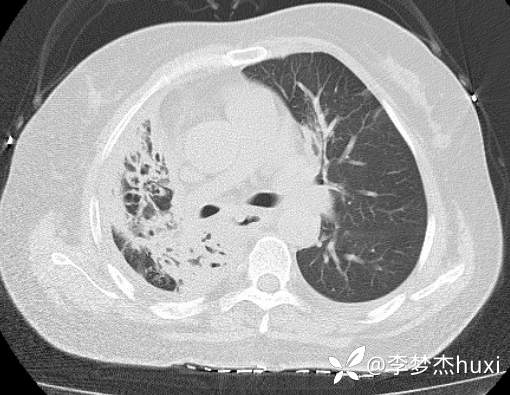

8.22治疗后的胸部CT: